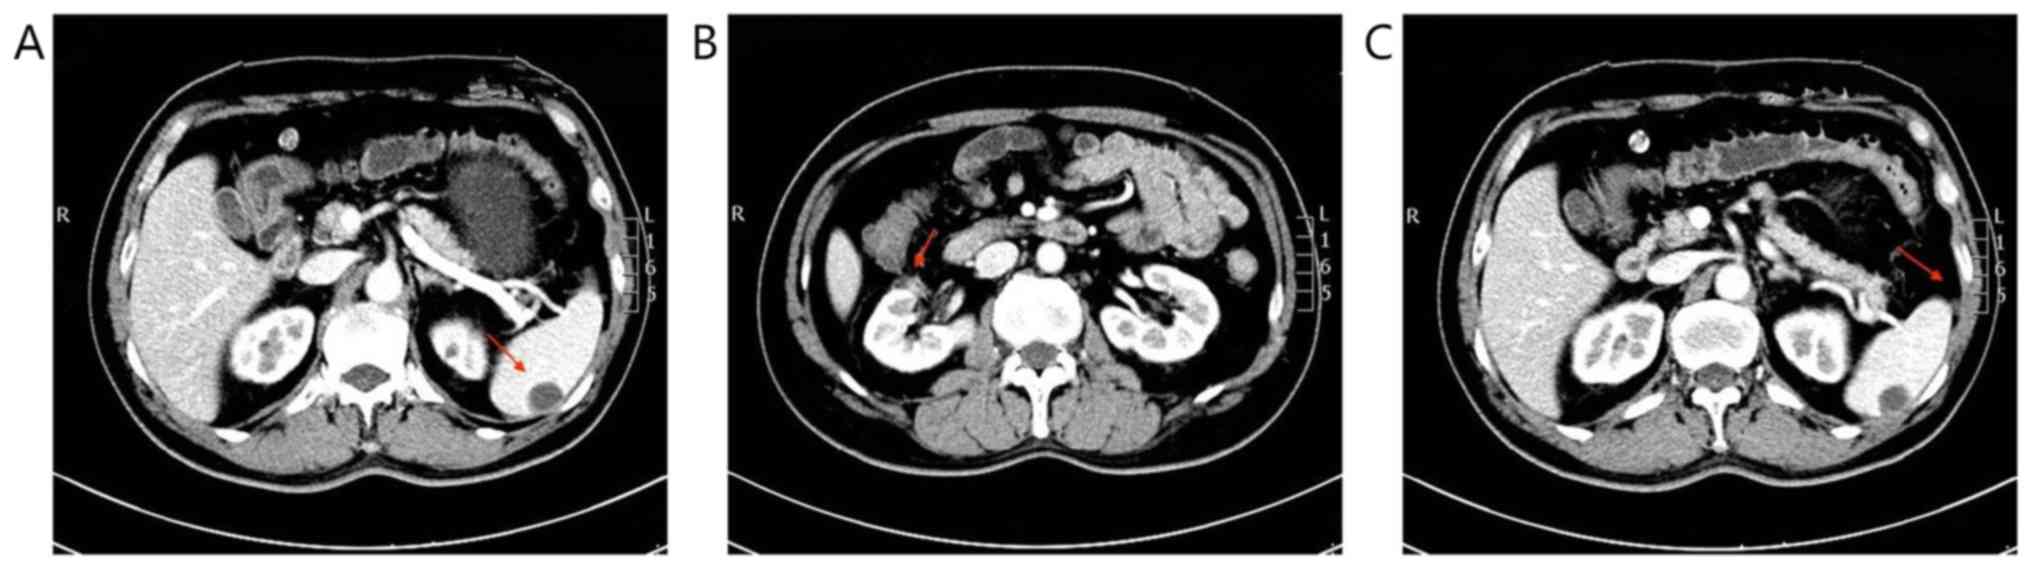

Figure 2

CT scanning before combination therapy in March 2018. (A) Spleen metastasis: The arrow indicates the spleen mass. (B) Local recurrence: The arrow indicates right renal mass. (C) Abdominal cavity metastasis: The arrow indicates abdominal cavity mass.

A 55-year-old male presented with a right renal mass on CT scan. He was diagnosed with renal clear cell carcinoma with sarcomatoid differentiation after robot-assisted laparoscopic resection of the local mass (Fig. 1). Adjuvant targeted therapy with sunitinib (50 mg/day; 2 weeks on, 1 week off) was performed for six cycles. On March 21st 2018, a CT scan revealed local recurrence, and spleen and abdominal cavity metastasis (Fig. 2). As a result of this, the patient was started on pembrolizumab (2 mg/kg once every 3 weeks) combined with sunitinib (37.5 mg/day; 2 weeks on, 1 week off) on March 27th 2018. After 4 months, the patient developed limb weakness and numbness of the extremities. Neurological examination showed paresthesia of the four extremities, absence of tendon reflex of the limbs, and a mild decrease in muscle strength of the limbs with a grade of 4/5, but no pathological reflex was observed. This patient had no history of GBS, and laboratory examination results showed no evidence of infection. Procalcitonin, c-reactive protein, influenza virus antibody, cytomegalovirus antibody, rubella virus antibody, herpes simplex virus antibody, Epstein-Barr virus antibody, detection of mycoplasma and chlamydia DNA, and hepatitis virus tests were all negative. Rheumatic immune disease was also ruled out. Magnetic resonance imaging of the brain and spinal cord was normal. Cerebrospinal fluid (CSF) analysis showed albuminocytologic dissociation (protein, 583.30 mg/l; cell count, 8,000/µl), and Pandy's test was positive. Electroneuromyography revealed acute motor and sensory axonal neuropathy (Fig. 3). Based on these results, the patient was diagnosed with GBS, which can be induced by pembrolizumab. Pembrolizumab was permanently discontinued due to this severe immune-related adverse event (irAE). The symptoms were gradually aggravated after oral treatment with dexamethasone (10 mg/day). The patient was then switched to intravenous immunoglobulin (IVIG; 0.4 g/kg for 5 days) along with prednisone (1 mg/kg per day). The patient's symptoms improved during 1 week of treatment. After 1 month, although he experienced difficulty with fine movements, he was able to walk and stand normally, and the doctors began to taper off the prednisone dosage. CT scan reexamination showed that the masses in the right kidney and abdominal cavity had disappeared, and the enhancement degree of spleen metastases was reduced (Fig. 4). No recurrence was observed during the 10 months of follow-up.